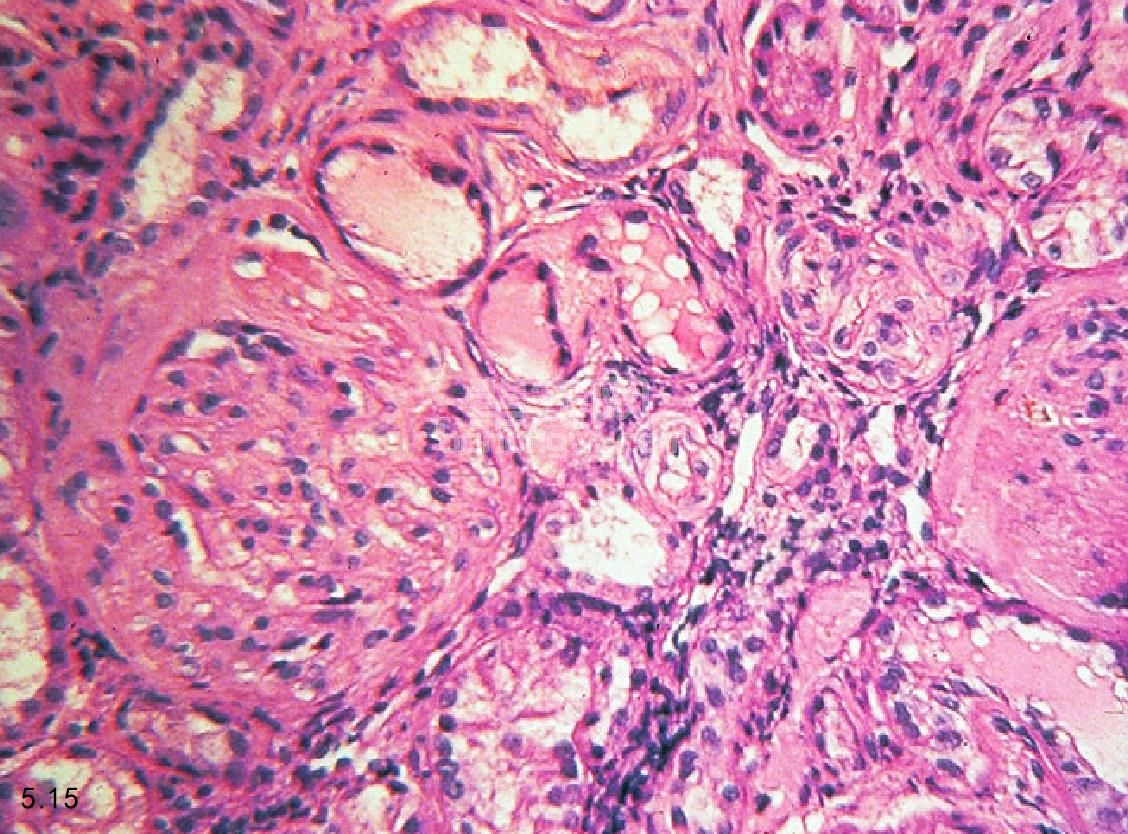

诊断 根据临床调查、身体检查(见以上部分)和实验室检查结果来确定是否患有CRF。典型的检查结果包括红细胞正常的色素性贫血、淋巴细胞减少、氮质血症、高磷酸盐血症和负离子升高引起的代谢性酸中毒。脂肪酶和淀粉酶比正常升高2.5~3倍,但不会出现胰腺炎。尿液检查显示为等渗尿、轻度蛋白尿(除非疾病过程特殊,涉及到了肾小球)和良性尿沉积物。在这些情况下,可以观察到管型,它们直径比较宽。在进行X线和超声诊断时,肾脏的大小、形状和密度会有异常。肾脏组织活检显示,在肾血管球硬化症和单核性间隙性渗透的纤维化时,肾小球和肾小管有不同程度的萎缩(图5.15和图5.16)。在表述氮质血症的症状和程度时会有很大差别。

图5.15和图5.16 犬慢性肾衰竭肾脏的组织病理学。图5.15肾血管球硬化症和单核性间隙性渗透病变。图5.16肾小管萎缩和间隙纤维化。